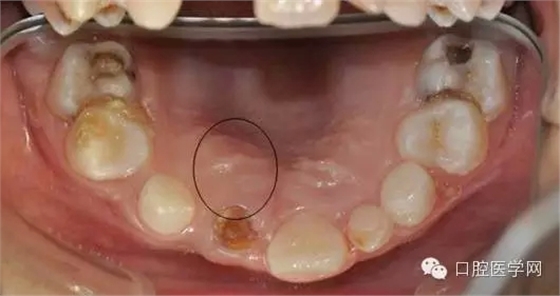

俺一般不喜歡浪費國家資源,能拍小牙片的堅決不拍CBCT.這個病例還真不敢輕易下刀。兩顆埋伏一二擠在一起,位置較深。讓步了,拍CT吧。

CBCT后影像

我們能夠更好的了解牙齒的立體空間結構.好東西哈,清晰。

腭側相有輕微隆起: